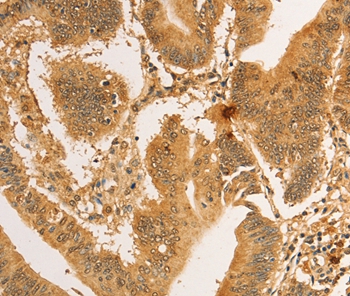

Immunohistochemical analysis of paraffin-embedded Human colon cancer tissue using #36167 at dilution 1/30.

Immunohistochemical analysis of paraffin-embedded Human lung cancer tissue using #36167 at dilution 1/30.